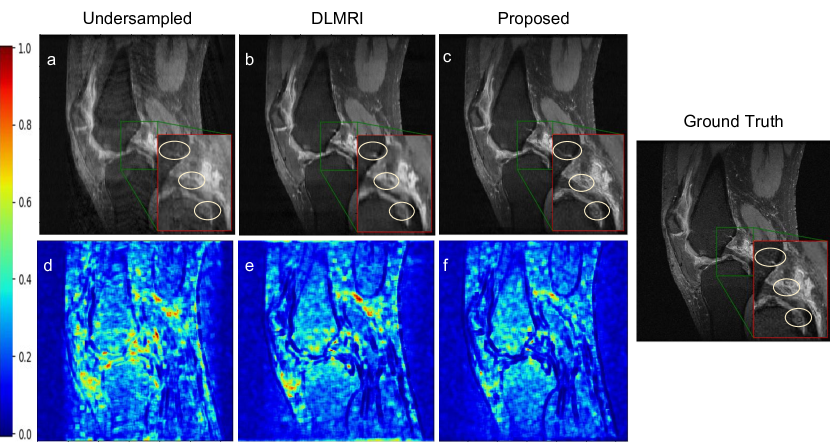

Refer to caption

Figure 3: Reconstruction results using 4×\times acceleration factor. (a), (d) Undersampled image and its error map, (b), (e) DLMRI reconstruction and its error map, (c), (f) Proposed reconstruction and its error-map, and ground truth.

Qualitative Analysis: Fig. 2 illustrates the contrastive results on recovery of fine-grained details using the edge-map extracted from an under-sampled image (Fig. 2(b,f)), DLMRI (Fig. 2(c,g)) and proposed method (Fig. 2(d,h)). We observe that the proposed network demonstrates maximal consistency in finer details with respect to the ground-truth. Fig. 3 highlights the differences with respect to the ground truth through a difference map and particularly focus on reconstruction of fine details in the region between the tibia and femur and the synovial membrane.